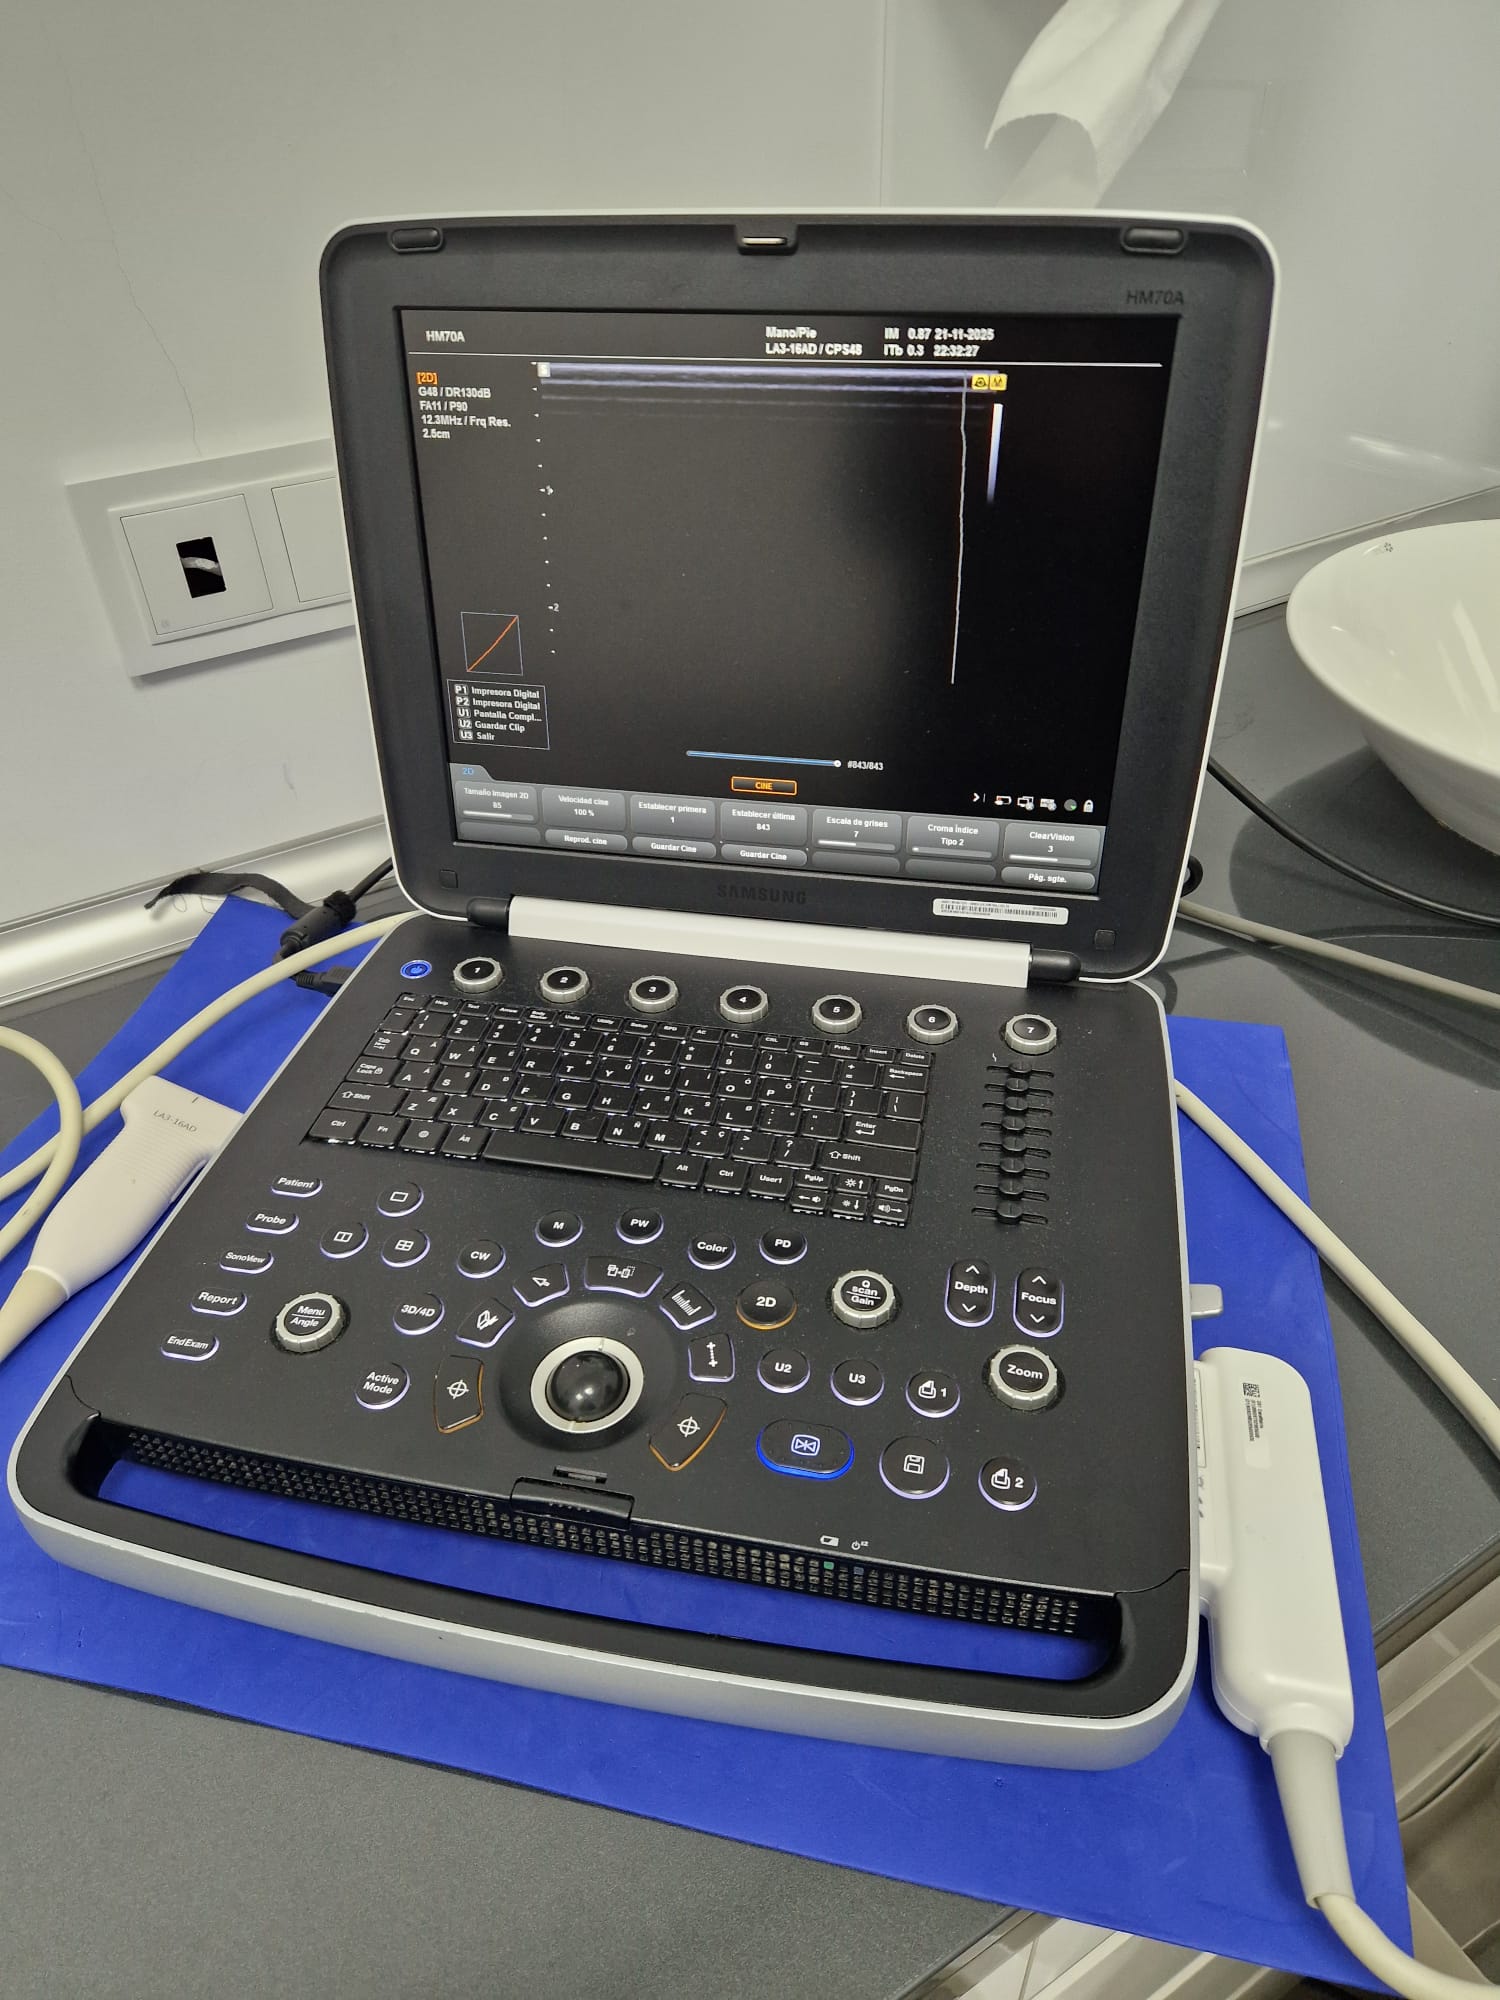

Samsung HM70A Plus

Samsung HM70A Plus

- El ecógrafo Samsung HM70 EVO es un dispositivo portátil de alto desempeño, diseñado para cubrir una amplia variedad de aplicaciones clínicas y adaptarse a distintos tipos de pacientes. Cuenta con un flujo de trabajo eficiente, gran resistencia y una calidad de imagen de alta definición, lo que permite su uso en múltiples entornos y escenarios clínicos.

- Sonda Lineal LA3-16AD y Stick LS6-15.

HQ-Vision ™

HQ-Vision ™ proporciona imágenes claras al mitigar las características de las imágenes de ultrasonido que están ligeramente borrosas que la visión real.